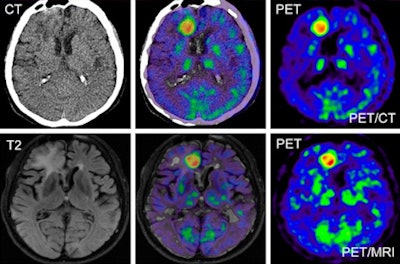

![]() |

| As an example of similar results with PET/CT and MRI, the images are of a 56-year-old patient with glioblastoma multiforme on the right side in the frontal area close to interhemispheric fissure. Top: PET/CT data show low-dose, noncontrast-enhanced CT scan (left), corresponding fusion image (center), and C-11 methionine PET image (right). Bottom: PET/MRI data show T2-weighted FLAIR image (left), fusion image (center), and PET image (right). |

"Our study indicates that hybrid PET/MRI of intracranial tumors using C-11 methionine or Ga-68 DOTATOC can be reliably performed," Boss and his colleagues wrote. "The image quality and quantitative data achieved using PET/MRI is similar to that using PET/CT."